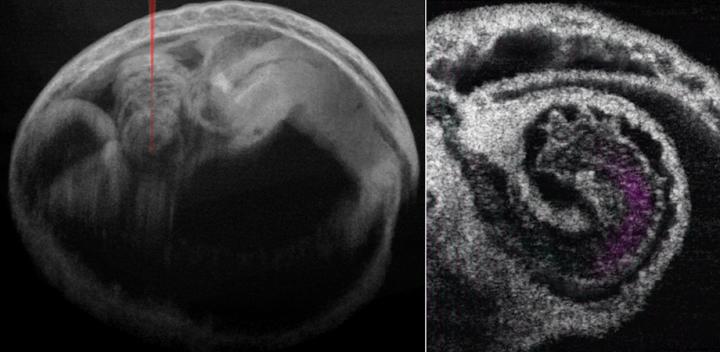

image: Mouse embryo and heart with blood flow. Wang and Larina, doi 10.1117/1.JBO.25.8.086001.

Shang Wang of the Stevens Institute of Technology and Irina Larina of the Baylor College of Medicine used cutting-edge 4D optical coherence tomography (OCT) to study the pumping mechanism underlying the developing mammalian heart for the first time. Their report, published in the peer-reviewed open access Journal of Biomedical Optics, demonstrates that 4D OCT imaging of mouse embryonic heart can provide unprecedented information about how the early mammalian heart works.

The unique imaging scales and dynamic contrasts offered by OCT enable millimeter-level imaging depth with a microscale resolution that is ideal for capturing the entire mouse heart at mid-gestation stages. OCT also provides a clear view of fine cardiac structures as well as blood flow. The high imaging speed of OCT together with post-acquisition synchronization allows reconstructing the fast dynamics of the beating heart.

There is much to be learned. Although the mechanism that pumps blood within the embryonic heart tube has traditionally been thought to be wavelike peristaltic contractions, Wang and Larina were able to offer a more detailed assessment using 4D OCT to integrate cardiodynamics and hemodynamics. Their pilot observations suggest that localized heart tube pumping in the ventricles functions through a combination of suction and pushing mechanisms.